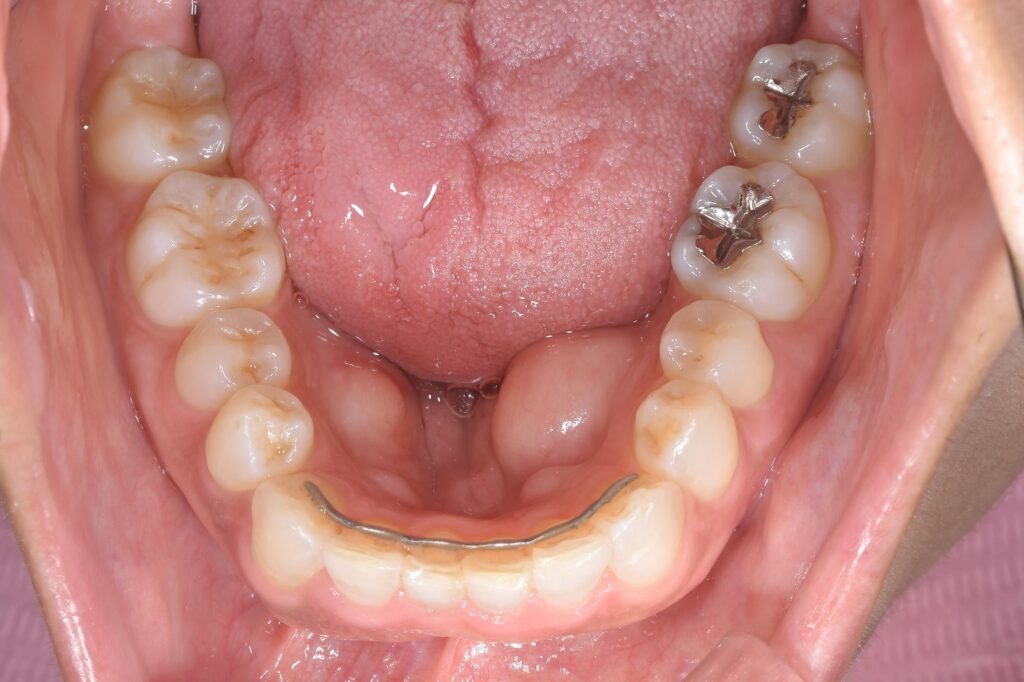

【治療終了時】

③矯正治療開始。(マウスピース矯正のインビザラインのみで施術)

④矯正終了後、上顎前歯は歯茎を整える手術施行。仮歯調整。

⑤上顎左3番目から右側3番目の歯(計6本)をセラミック(ジルコニア)を装着。